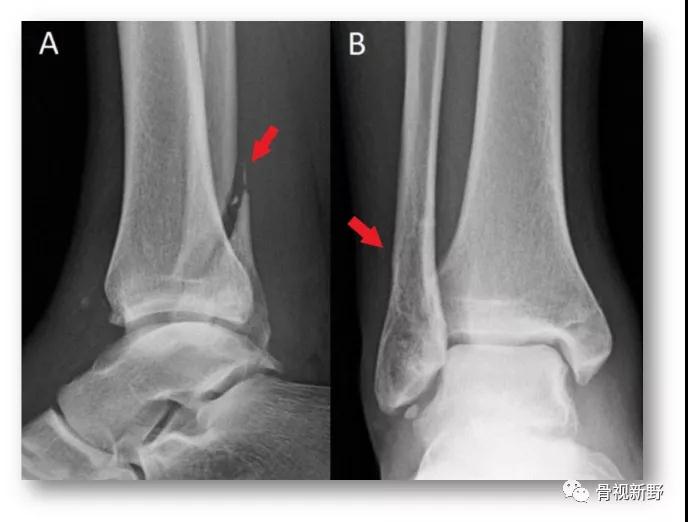

手法复位前X光片

氯胺酮基础麻醉下,患者屈膝位,踝关节背屈位牵引,通过足的旋后、内旋给距骨施加一个前向力,以大体复位踝关节(此时如沿腓骨远、近端触诊,会发现腓骨仍然交锁于胫骨后方)。腓骨解锁:一手手指置于腓骨干后内侧面并向前、外推挤,另一手置于胫骨干维稳、并作反向对抗。触诊发现腓骨解锁(如下图)。

手法复位成功(X光片)